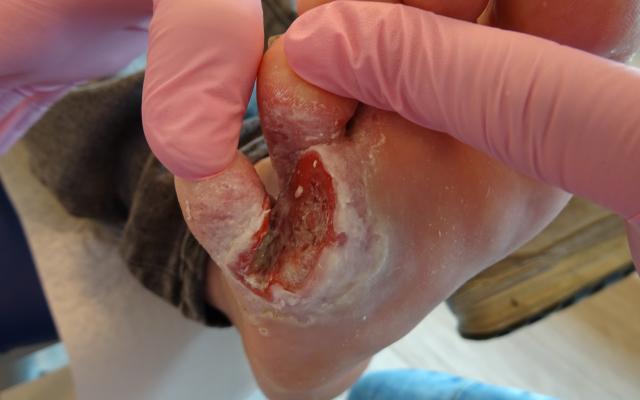

De huisarts verwees een 60-jarige Kaukasische man naar de dermatoloog vanwege een niet-genezend ulcus tussen de 4e en 5e teen van de rechter voet. Het ulcus bestond al enkele maanden en was tweemaal een porte d’entrée geweest voor erysipelas. Bij lichamelijk onderzoek constateerde de dermatoloog een solitair, interdigitaal gelokaliseerd en riekend ulcus met weke randen (figuur a). Diverse lokale behandelingen, waaronder alginaat, antimycoticum en curettage, bewerkstelligden geen effect. Nadat het ulcus aanvankelijk verbeterde door behandeling met systemische antimycotica en antibiotica, nam het in grootte toe en toonde het opgeworpen randen (figuur b). Ruim 3 maanden na het eerste polikliniekbezoek…